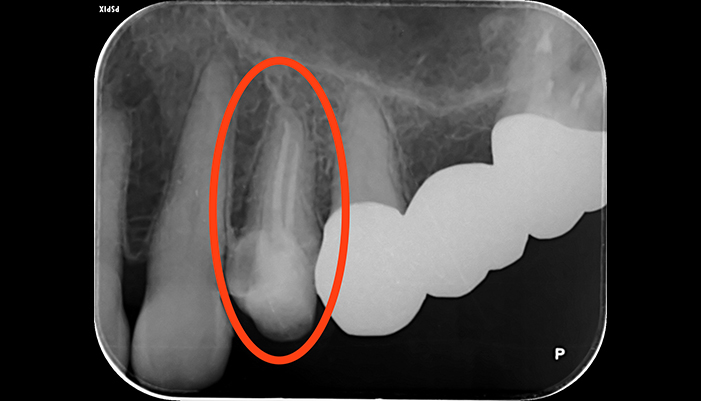

治療前

治療後

| 主訴 | 歯茎が腫れている |

|---|---|

| 治療期間 | 2回 |

| 費用 | 再根管治療154,000円(税込)+ ファイバーコア44,000円(税込)= 198,000円(税込) |

| 治療内容 |

ラバーダムを用いて無菌的な環境下で根管治療を行いました。 マイクロスコープ下で虫歯を完全に取り切り、NiTiファイルを用いた根管形成、薬液や超音波器具による洗浄、その後根管内をさらに消毒するため水酸化カルシウムを入れて仮の蓋をしました。 2回目は体に馴染みの良い材質による充填、被せ物を支え、再感染しないように土台を立てました。 |